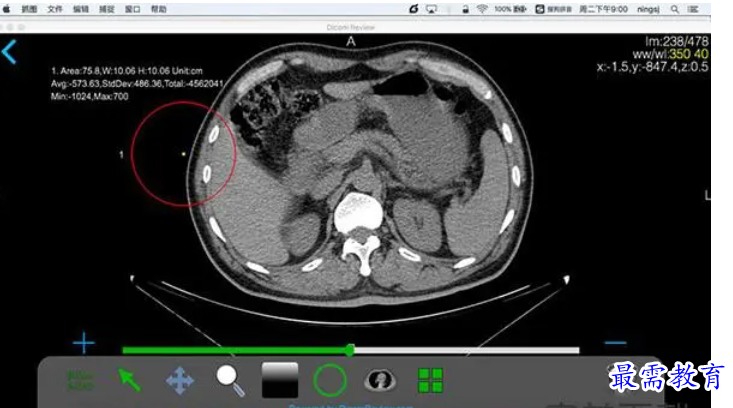

DicomReview Mac版是一款Mac上的医学软件,DicomReview是最好的私人影像工作站。它能接受来自CT,MR,DR,PET/CT等医疗设备的Dicom文件,支持2D浏览,3D显示,MIP重建,MPR重建等。他使医生更加方便的浏览医学影像,并且和朋友们交流分享。

DicomReview启动后,提供符合DICOM标准的C-STORE服务。安装DicomReivew的Mac就相当于PACS网络中的一个终端,能够和PACS网络中其他的终端传递Dicom医学数据。如果您的Mac和CT、MR等医学影像设备在同一个局域网内,DicomReview App能够自动发现局域网内的影像设备,自动和这些设备建立数据链接。